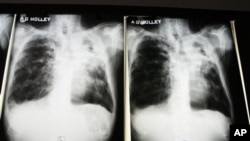

Estirpes de Tuberculose que são resistentes aos múltiplos medicamentos existentes representam uma grande ameaça a qual pode espalhar-se rapidamente segundo indicou a Organização Mundial de Saúde (OMS) e o Fundo Global para Combater a SIDA, Tuberculose e Paludismo.

Estas duas organizações estão a fazer campanha para obterem fundos a serem usados no combate à segunda doença infecciosa mais mortal no mundo: Tuberculose (TB).